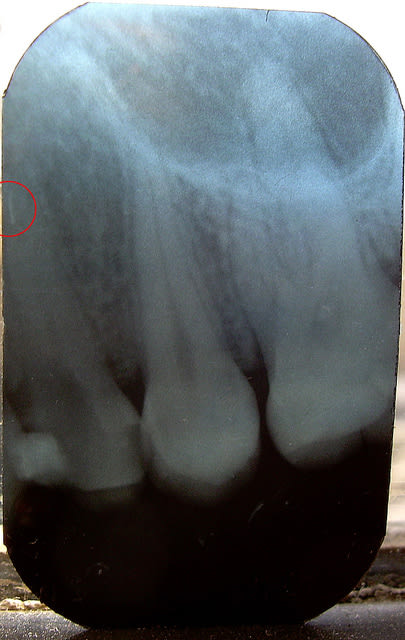

VOILA LES RADIO, celle pre op et lime en place pour la LT n y sont pas (restees au cab),la verif c est celle prise quand j ai senti que ca coincait a l apex du canal vestibulaire, la derniere c est avant de couper les cones. Avec du recul, j aurai du faire une radio defilee pour dissocier mes 2 canaux, mais bon...